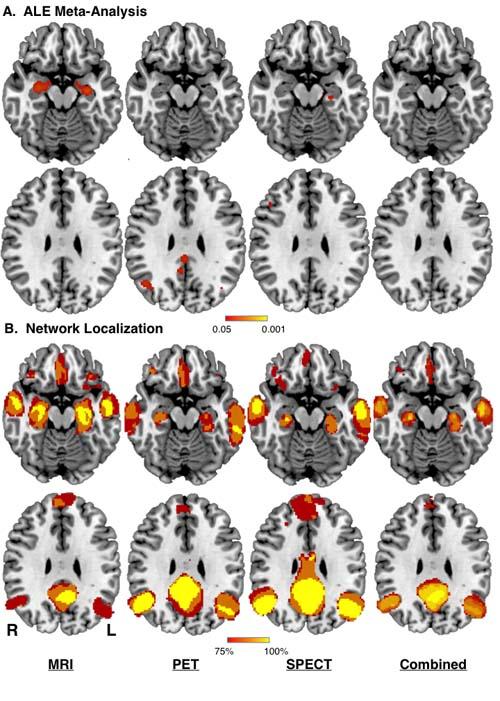

A neural mapping approach that pegs results from more than two dozen previous Alzheimer's studies found that reproducibility improves when trying to isolate symptoms to a brain network rather than a single area of the brain.

This is the first study to use "meta analysis network mapping" to essentially show results from prior studies that can't be reproduced to a single location in the brain are mappable to a distributed network, said Ryan Darby, MD an assistant professor of neurology at Vanderbilt University Medical Center, who is first author of the paper that will run in Brain in January.

Of the 26 Alzheimer's studies examined, reproducibility to a specific region came to 20 to 30 percent - a low rate that highlights one of the persistent challenges in studies. But when looking at reproducibility to a network, the rate surged to 100 percent.